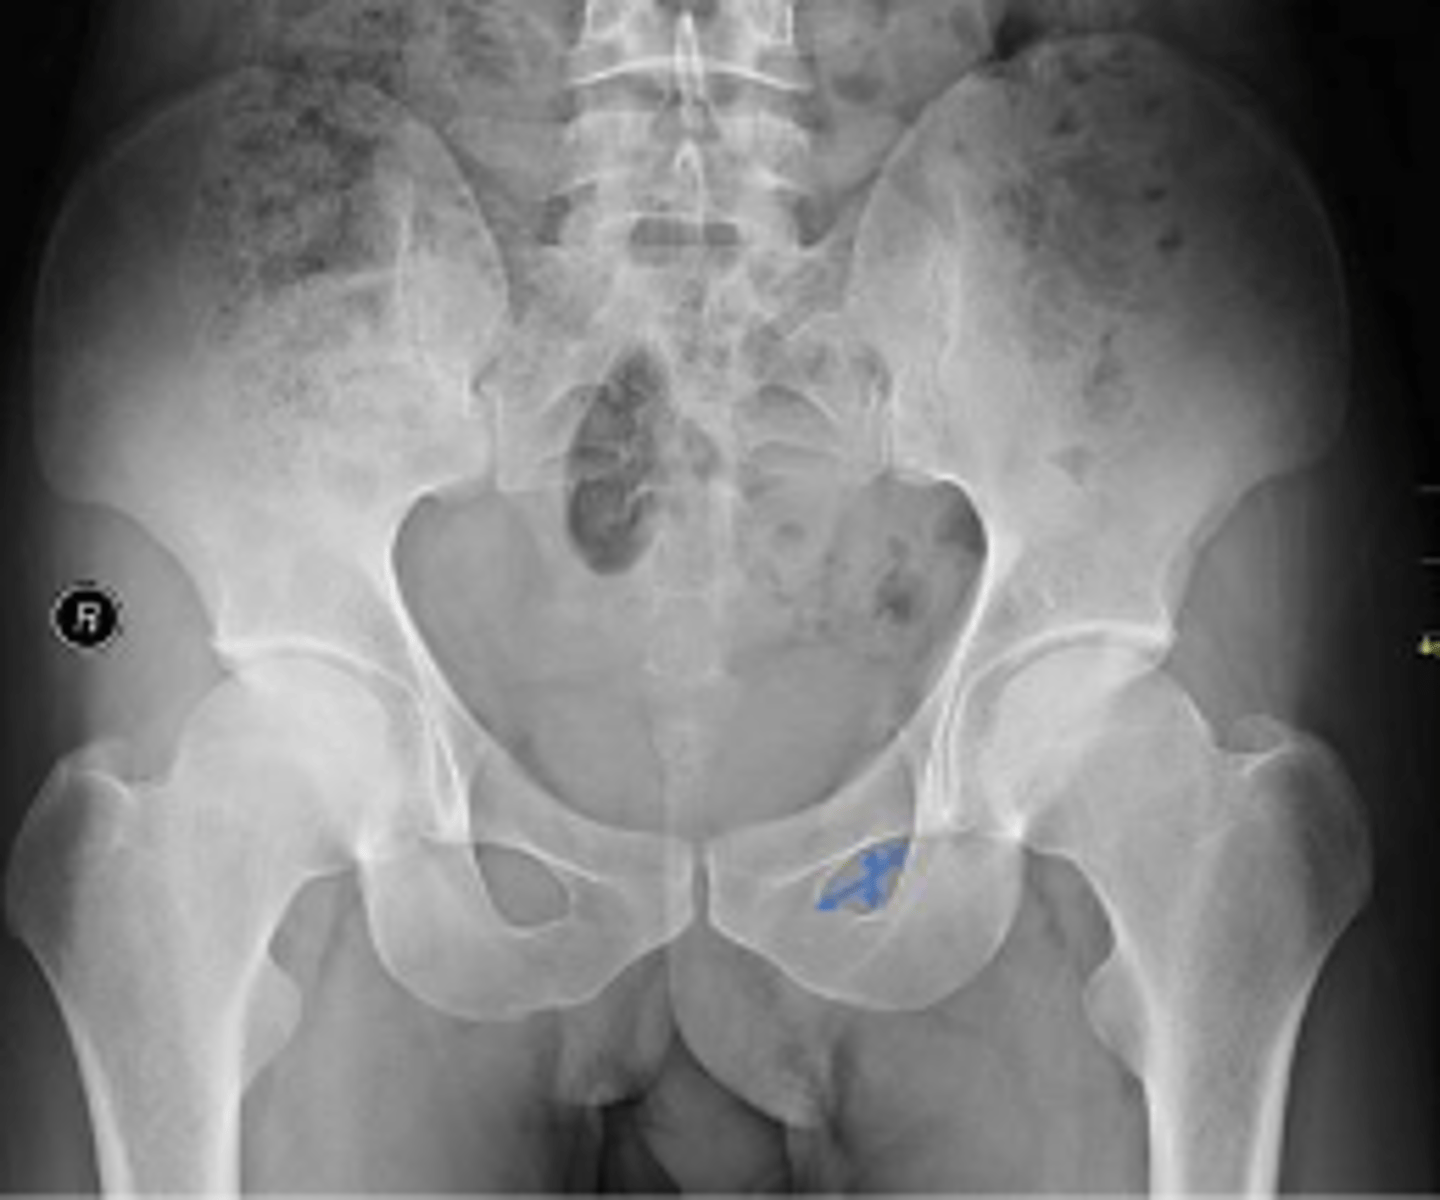

AP pelvis or bilateral hips

What is the name of the radiographic view?